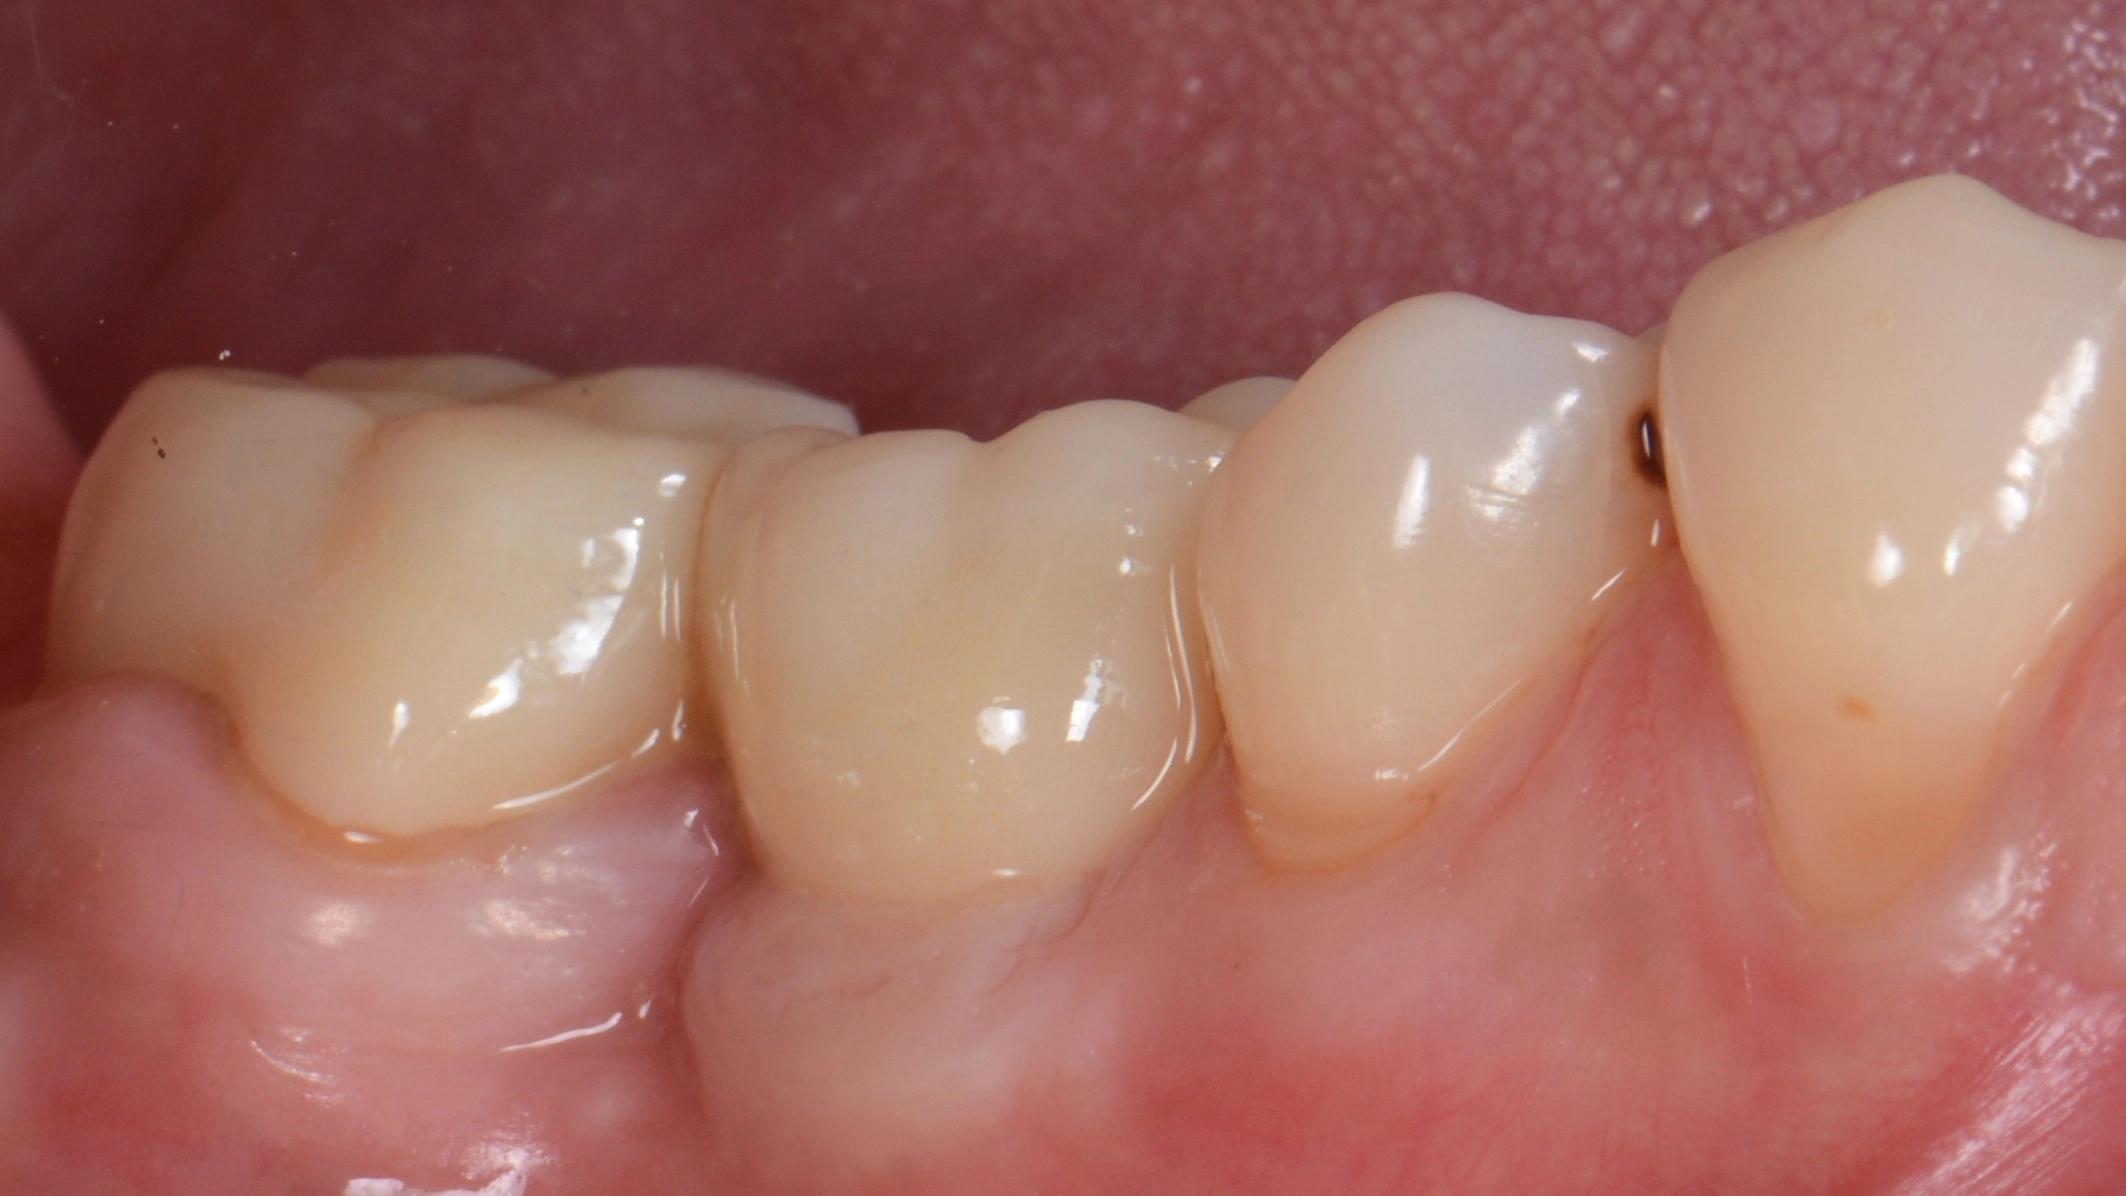

В данном кейсе не стали прибегать к ортодонтическому лечению, а просто установили имплантат MIS С1

Далее провизорное протезирование с препарированием зуба 47, и после формирования профиля постоянное протеизрование коронками на цементной фиксации на имплантате и на зубе. Зачастую, не всегда вижу необходимость в апрайте семерок, особенно, если в дальнейшем их еще и требуется покрыть коронкой.